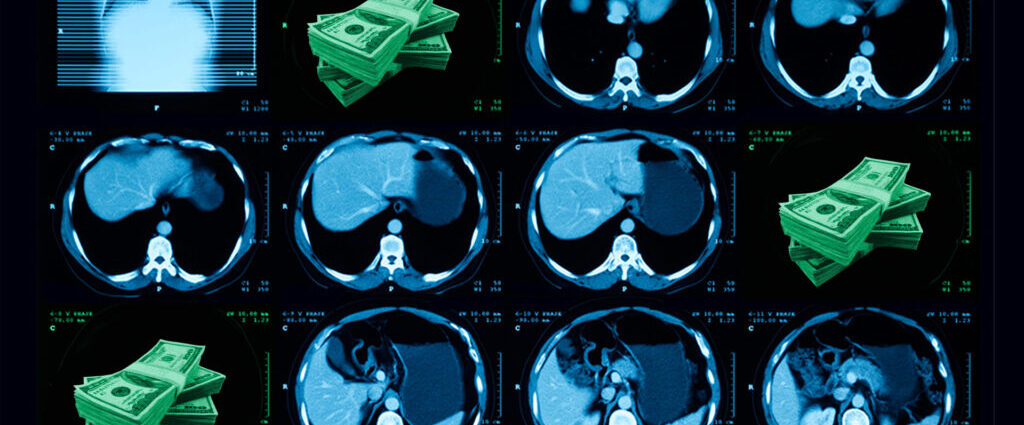

In a CT scan, coronary artery calcium shows up as distinct, bright pixels. It looks like salt in the pepper of the heart. The more calcium, the higher a patient’s risk of a heart attack.

Often, a cardiologist looks for those bright spots on purpose: They’ll grab snapshots of the heart between beats, to get the clearest possible view of the coronary arteries. But calcium is also visible on zoomed-out chest CTs that aren’t synchronized with the heart. Every year, patients receive 19 million of those more general scans — to screen for lung cancer, or investigate a persistent cough — and an eagle-eyed radiologist can report any incidental calcium they spot.

But even as heart disease remains the top cause of death in the United States, an estimated 20% to 40% of that incidental calcium goes unreported. “We need to find more of these patients,” said Ami Bhatt, chair of the Food and Drug Administration’s Digital Health Advisory Committee and chief innovation officer of the American College of Cardiology.